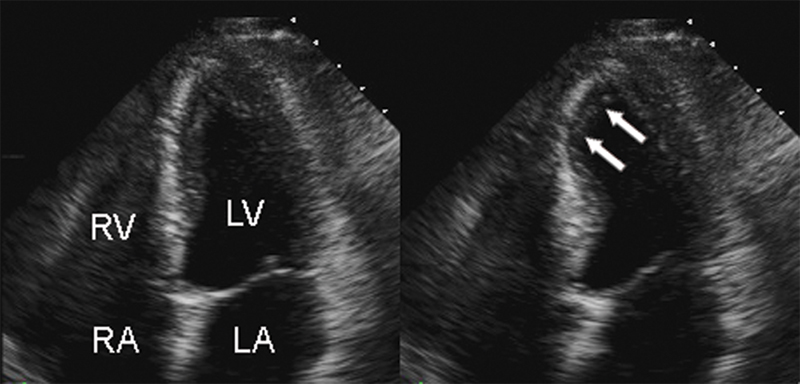

فحوصات تشخيصية لبعض امراض القلب والشرايين التاجية